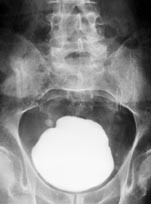

Røntgen oversikt abdomen viste en stor forkalkning i blæreregionen (fig 1). Intravenøs urografi viste forsinket utskilling fra venstre nyre og utvidelse av begge nyrebekkener og urinledere. Serum-kreatinin var normal. Cystoskopi var ikke mulig å gjennomføre, fordi steinen hindret cystoskopet i å passere gjennom en sklerotisk blærehals. Preoperativ miksjonsliste ble ikke ført, og det ble ikke gjort urinstrømsmåling.

Steinen bestod hovedsakelig av kalsiumoksalat, veide 660 g, opptok et volum på 300 ml målt ved væskefortrengning og målte 9,6 ⋅ 8,5 ⋅ 7,2 cm3 (fig 2).